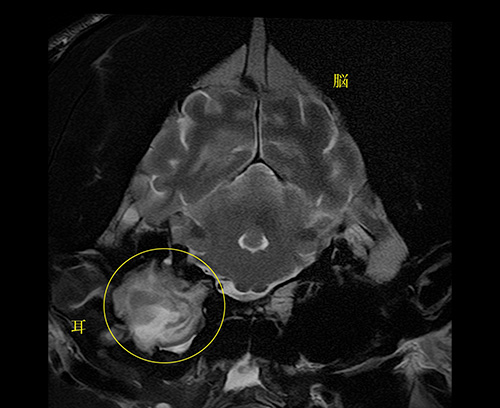

下垂体腫瘍(脳)

脳腫瘍